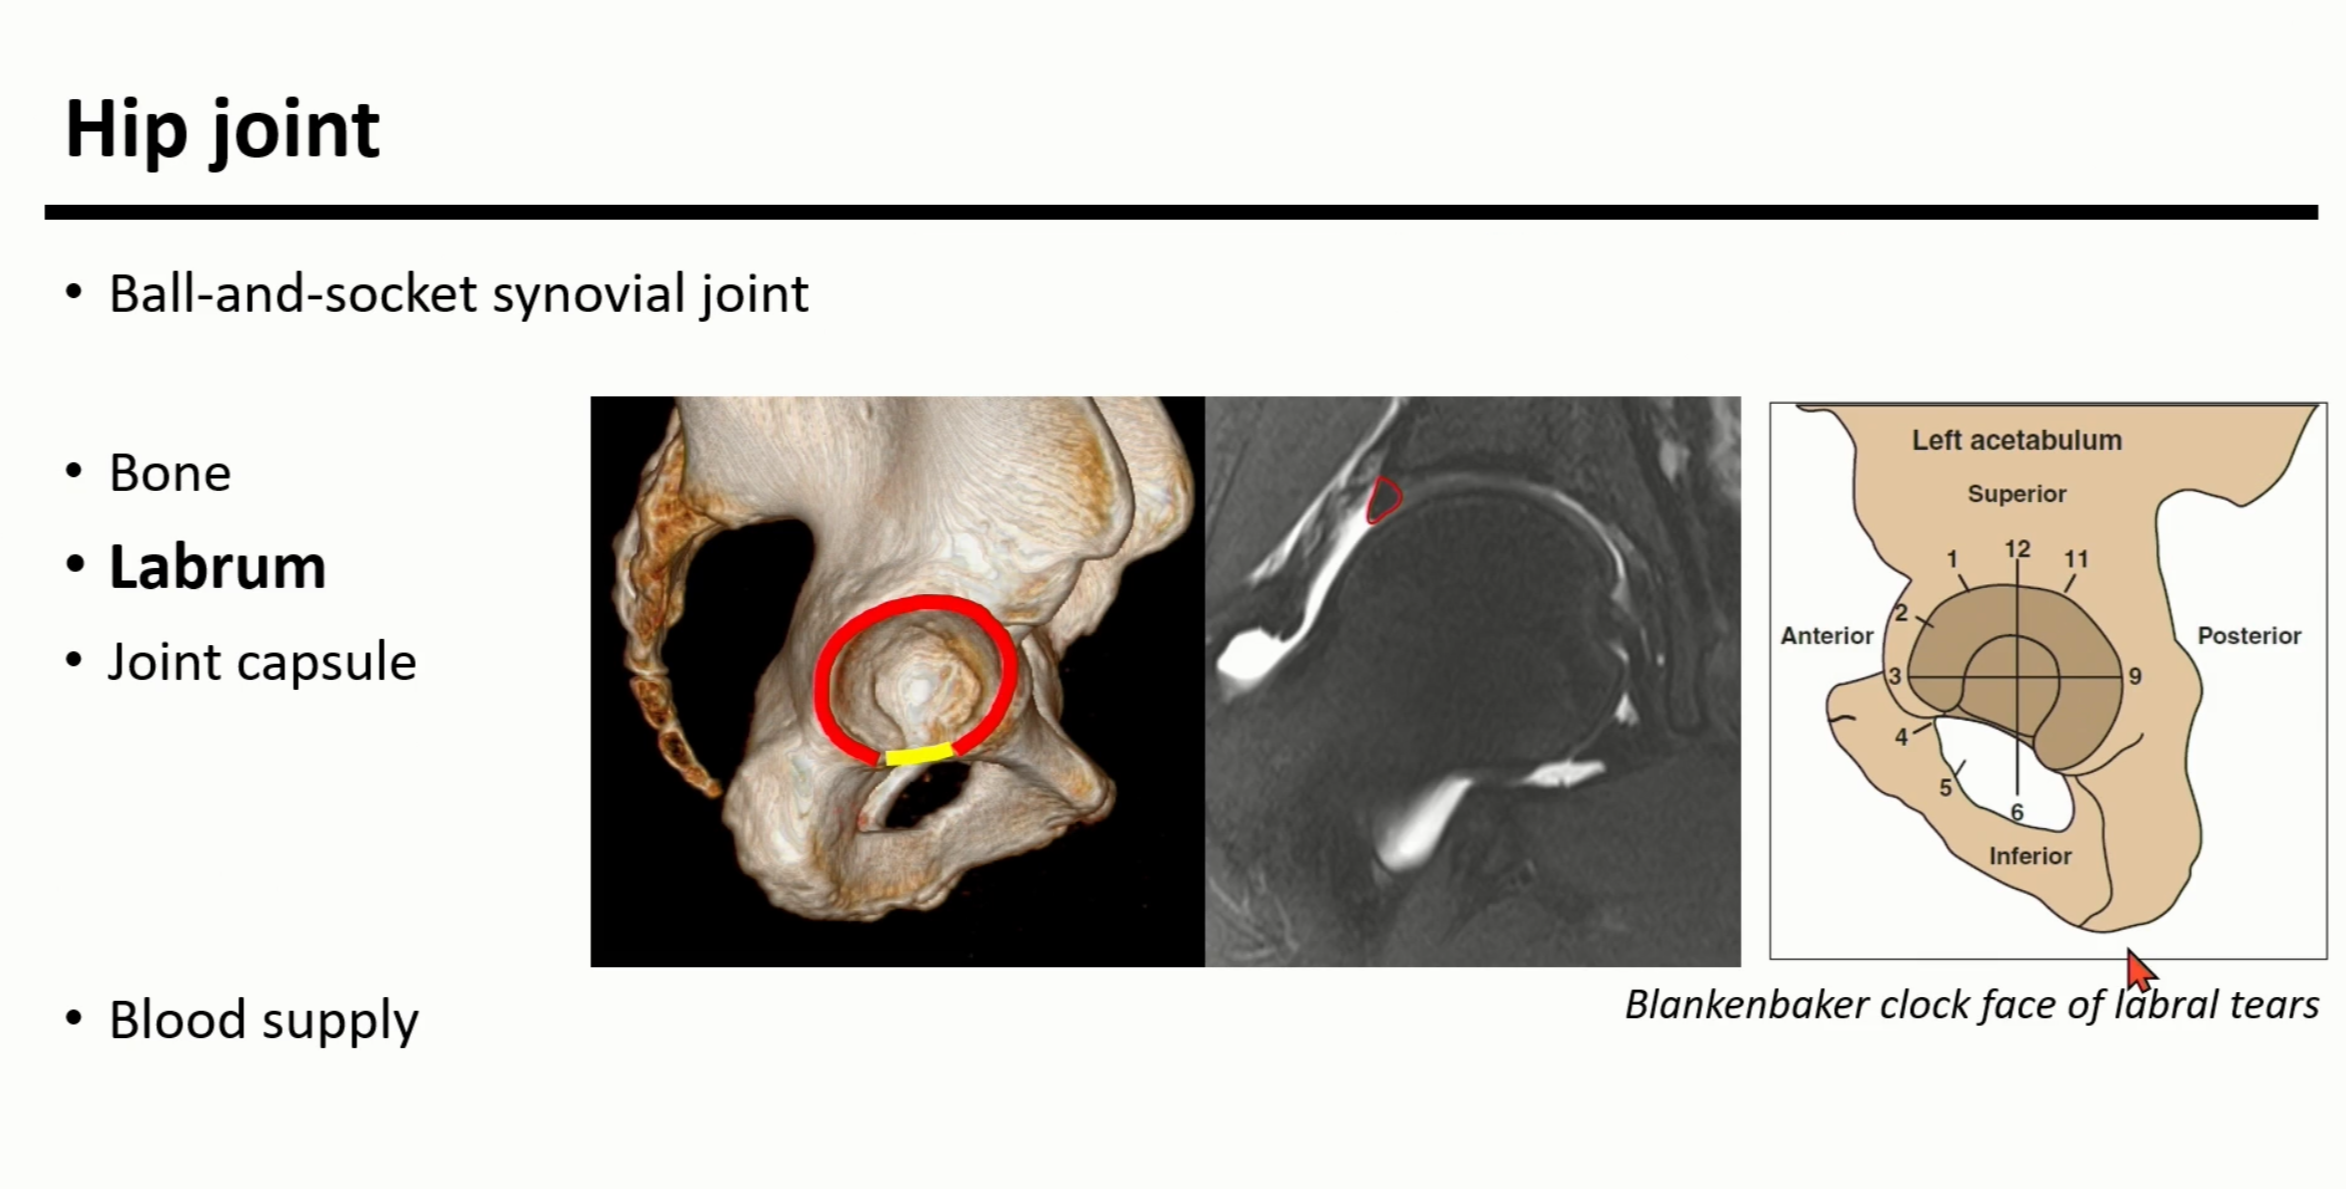

Labrum은 acetabular rim을 따라서 붙어있는 fibrocartileaginous structure(빨간색으로 표시됨)

(노란색은 transverse ligament) MRI상에서 hypo-intense한 triangular하게 관찰됨.